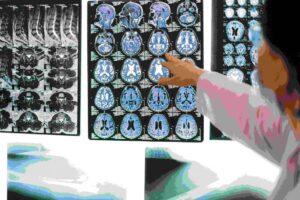

Smrtonosni misterij: Gotovo 100 ljudi oboljelo od tumora na mozgu, svi su išli u istu srednju školu!

Na papiru zvuči kao zaplet holivudskog igranog filma ili najnoviji dio misteriozne serije. U stvari, priča Al Lupiana je stvarna.…